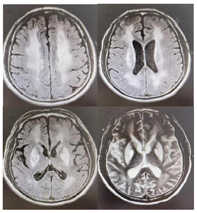

复查头颅MRI(2022年8月16日):脑实质内多发异常信号,考虑符合缺血缺氧性脑病改变,其中双侧豆状核凝固坏死,苍白球坏死,双侧枕叶缺氧性改变,伴皮层坏死;双侧乳突炎(图2)。

本例患者酒精中毒性脑病合并缺血缺氧性脑病,入院时患者神志欠清,查体不能配合,通过HBO治疗联合常规治疗后,患者神志、认知功能均在持续改善,四肢肌张力较前下降,但是通过患者7月26日和8月16日的头颅MRI可以得出,患者脑部组织的缺血缺氧损伤是处于进展加重的过程,与患者临床表现不相符,考虑是因为HBO治疗的介入,一方面及时遏制住了脑部缺血缺氧的继续损伤,避免了病情的进一步恶化,另一方面很大程度改善脑部组织缺氧状态,促进了脑组织的修复,导致患者临床症状得到了改善,而患者影像学改变呈加重表现是因为在病灶动态变化上,MRI病灶信号消退较临床症状和体征恢复为迟[ix],所以临床症状和体征与MRI改变并非并行,由此可以得出酒精中毒性脑病患者神经功能恢复情况与HBOT的治疗时机有着密切关联,具体有待进一步研究。本例研究患者在常规治疗的基础上联合HBOT 2个疗程后,临床主要症状得到明显改善,智能、意识障碍明显好转,疗效显著,说明常规治疗联合HBOT,可以改善脑部缺氧状态,修复受损脑组织和神经组织,提高临床治疗效果,同时为患者的功能康复奠定良好基础,临床应用价值显著。另外,虽然HBOT疗效肯定,耐受性良好,可明显且快速改善患者的临床症状,但依然不能替代戒酒及相应药物治疗,只有在综合治疗的基础上配合HBOT才有可能获得更好的治疗效果。